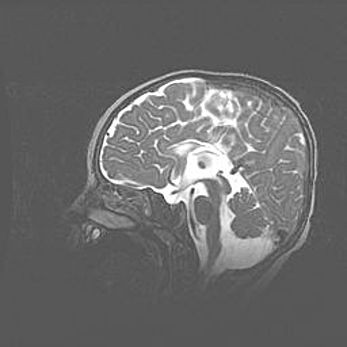

Открытая гидроцефалия.

Возраст: 9 месяцев 12 дней

Вес: 6800 г

Пол: мужской

Окружность головы: 41,5 см

Срок гестации: 28 недель

Гидроцефалия головного мозга у новорожденных имеет характерный признак: опережающий рост окружности головы приводит к визуально хорошо определяемой гидроцефальной форме сильно увеличенного в объёме черепа. Детские неврологи определяют следующие симптомы гидроцефалии у грудничков: выбухающий напряжённый родничок, частое запрокидывание головы, смещение глазных яблок к низу.